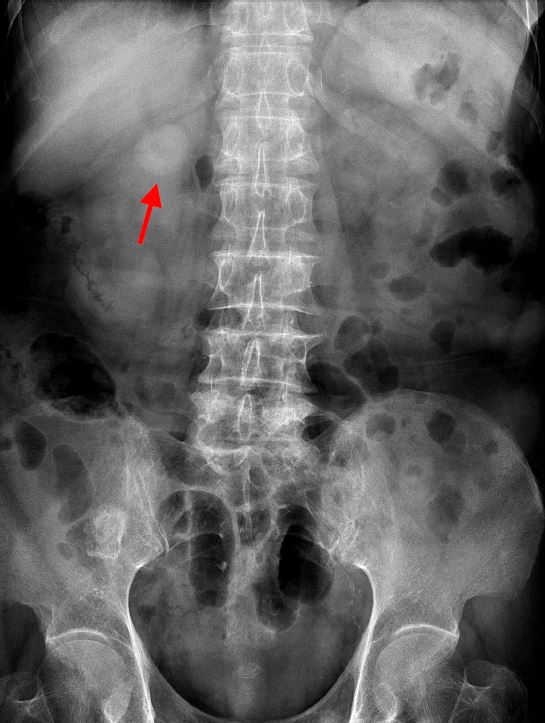

A. Hepatosplenomegaly

B.Right abdominal mass

C.Left abdominal mass

D.Retroperitoneal mass